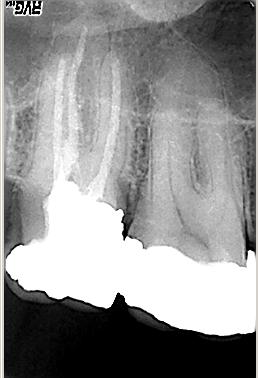

Zustand unmittelbar vor Behandlungsbeginn

Zustand unmittelbar vor Behandlungsbeginn im Juni 2003. Die Fraktur des distalen Zahnanteils hat die Patientin jetzt zur Einwilligung in die Behandlung motiviert. Auffällig ist in dieser Projektion die besonders starke Krümmung der mb Wurzel sowie die knochennahe Defektlage distal. Es erfolgte zunächst die Kariesentfernung gefolgt von einer chirurgischen Kronenverlängerung zur Herstellung der biologischen Breite sowie Ermöglichung des sog. Ferrule-Effektes. Danach wurde der Zahn adhäsiv aufgebaut. Erst jetzt wurde mit der eigentlichen WKB begonnen